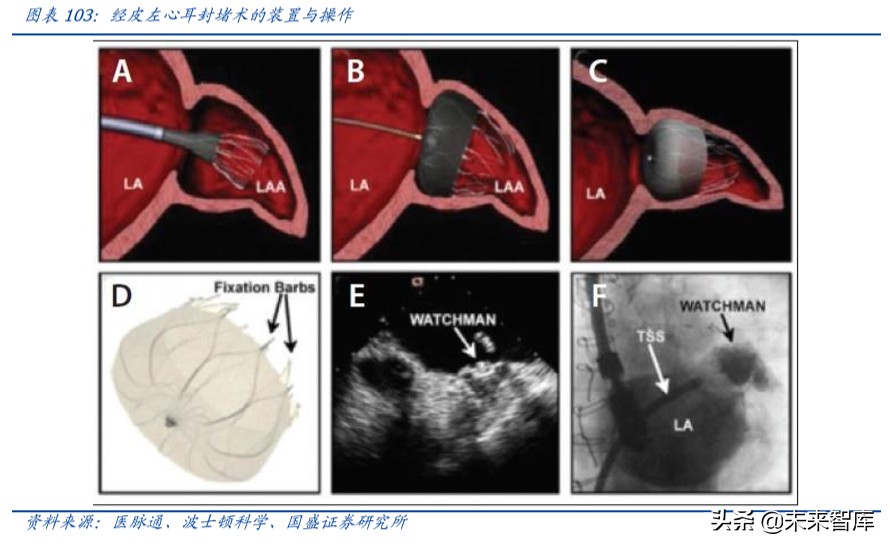

左心耳封堵器:有效预防房颤卒中,市场空间巨大

➢ 国内房颤患者数量巨大:左心耳由于具有特殊的生理位置,90%房颤患者卒中的血 栓来自心脏左心耳,对于无法长期口服抗凝药的患者,左心耳封堵是解决房颤患者 发生缺血性脑卒中的有效治疗方法。据《中国心血管病报告 2018》显示,中国≥35 岁居民的房颤患病率为 0.71%,目前全国房颤患者约有 990 万人。

➢ 左心耳封堵器有效降低卒中事件:CAP(Continued Access to PROTECT-AF)与 CAP2 (Continued Access to PREVAIL)是迄今为止左心耳封堵器(LAAC)样本量最大、 随访时间最长的注册研究。2019 年底这两项研究于 JACC 主刊发布其 5 年随访结 果:CAP 共纳入 566 例患者,平均随访 50.1 个月,CAP2 纳入 578 例患者,平均随 访 50.3 个月,总体手术成功率高达 94%。五年随访结果显示,两组患者出血性卒 中事件均显著降低,分别为 0.17/100 和 0.09/100 患者年,缺血性卒中的发生率为 1.30/100 和 2.20/100 患者年。全因卒中相比基于 CHA2DS2-VASc 评分的预测值显 著降低了 78%和 69%。这一研究结果充分揭示了 LAAC 的安全性和有效性,可作为 房颤血栓高危人群的优选治疗。

➢ 左心耳封堵在中国起步较晚但发展迅速:我国于 2014 年开展了左心耳封堵术的初 步应用,2015 年中国心房颤动认识和治疗建议中将左心耳封堵术推荐级别升高至 IIa,证据级别为 B 类,主要适用于不适合长期规范抗凝或在长期规范抗凝基础上仍 出现卒中事件或出血高危患者(HAS-BLED 评分在 3 分以上)。波士顿科学的 WATCHMAN™是目前全球唯一获得 FDA 认证的左心耳封堵器,截止 2018 年初美国 左心耳封堵例数已超过 15,000 例,波士顿科学预计 2018 年 LAAC 全球市场规模为 4亿美元,到2025年可达20亿美元,年复合增长超过25%。中国2017年WATCHMAN ™植入例数也超过了 1,500 例。目前开展左心耳封堵的单位已遍及全国 31 省市,接 近 200 家医院,而且手术量超过 100 台的中心已达 11 家。

➢ 左心耳封堵器潜在市场空间巨大:2016 年 6 月先健科技 LAmbre 左心耳封堵器获得 CFDA 批准后,2016 年营收 320 万,2017 年营收 2,110 万元, 2019 年上半年 LAmbre 左心耳封堵器营收 2590 万元,同比增长约 47.2%。目前我国仅 5 家公司产品获批 上市,进口器械有 Watchman 封堵器(美国波士顿科学)、 ACP 封堵器(圣犹达,美 国雅培收购),国产器械有 LAmbre 左心耳封堵器(先健科技)、北京迈迪顶峰医疗 的“左心耳闭合系统”和上海普实医疗的“左心耳封堵器系统”。乐普医疗目前左心 耳封堵器已通过 NMPA 注册申报,并通过 GMP 审核,预计 2020 年上市。预计未来 公司重磅产品上市,有望在封堵器领域逐步抢占市场份额,带来较大业绩增长。